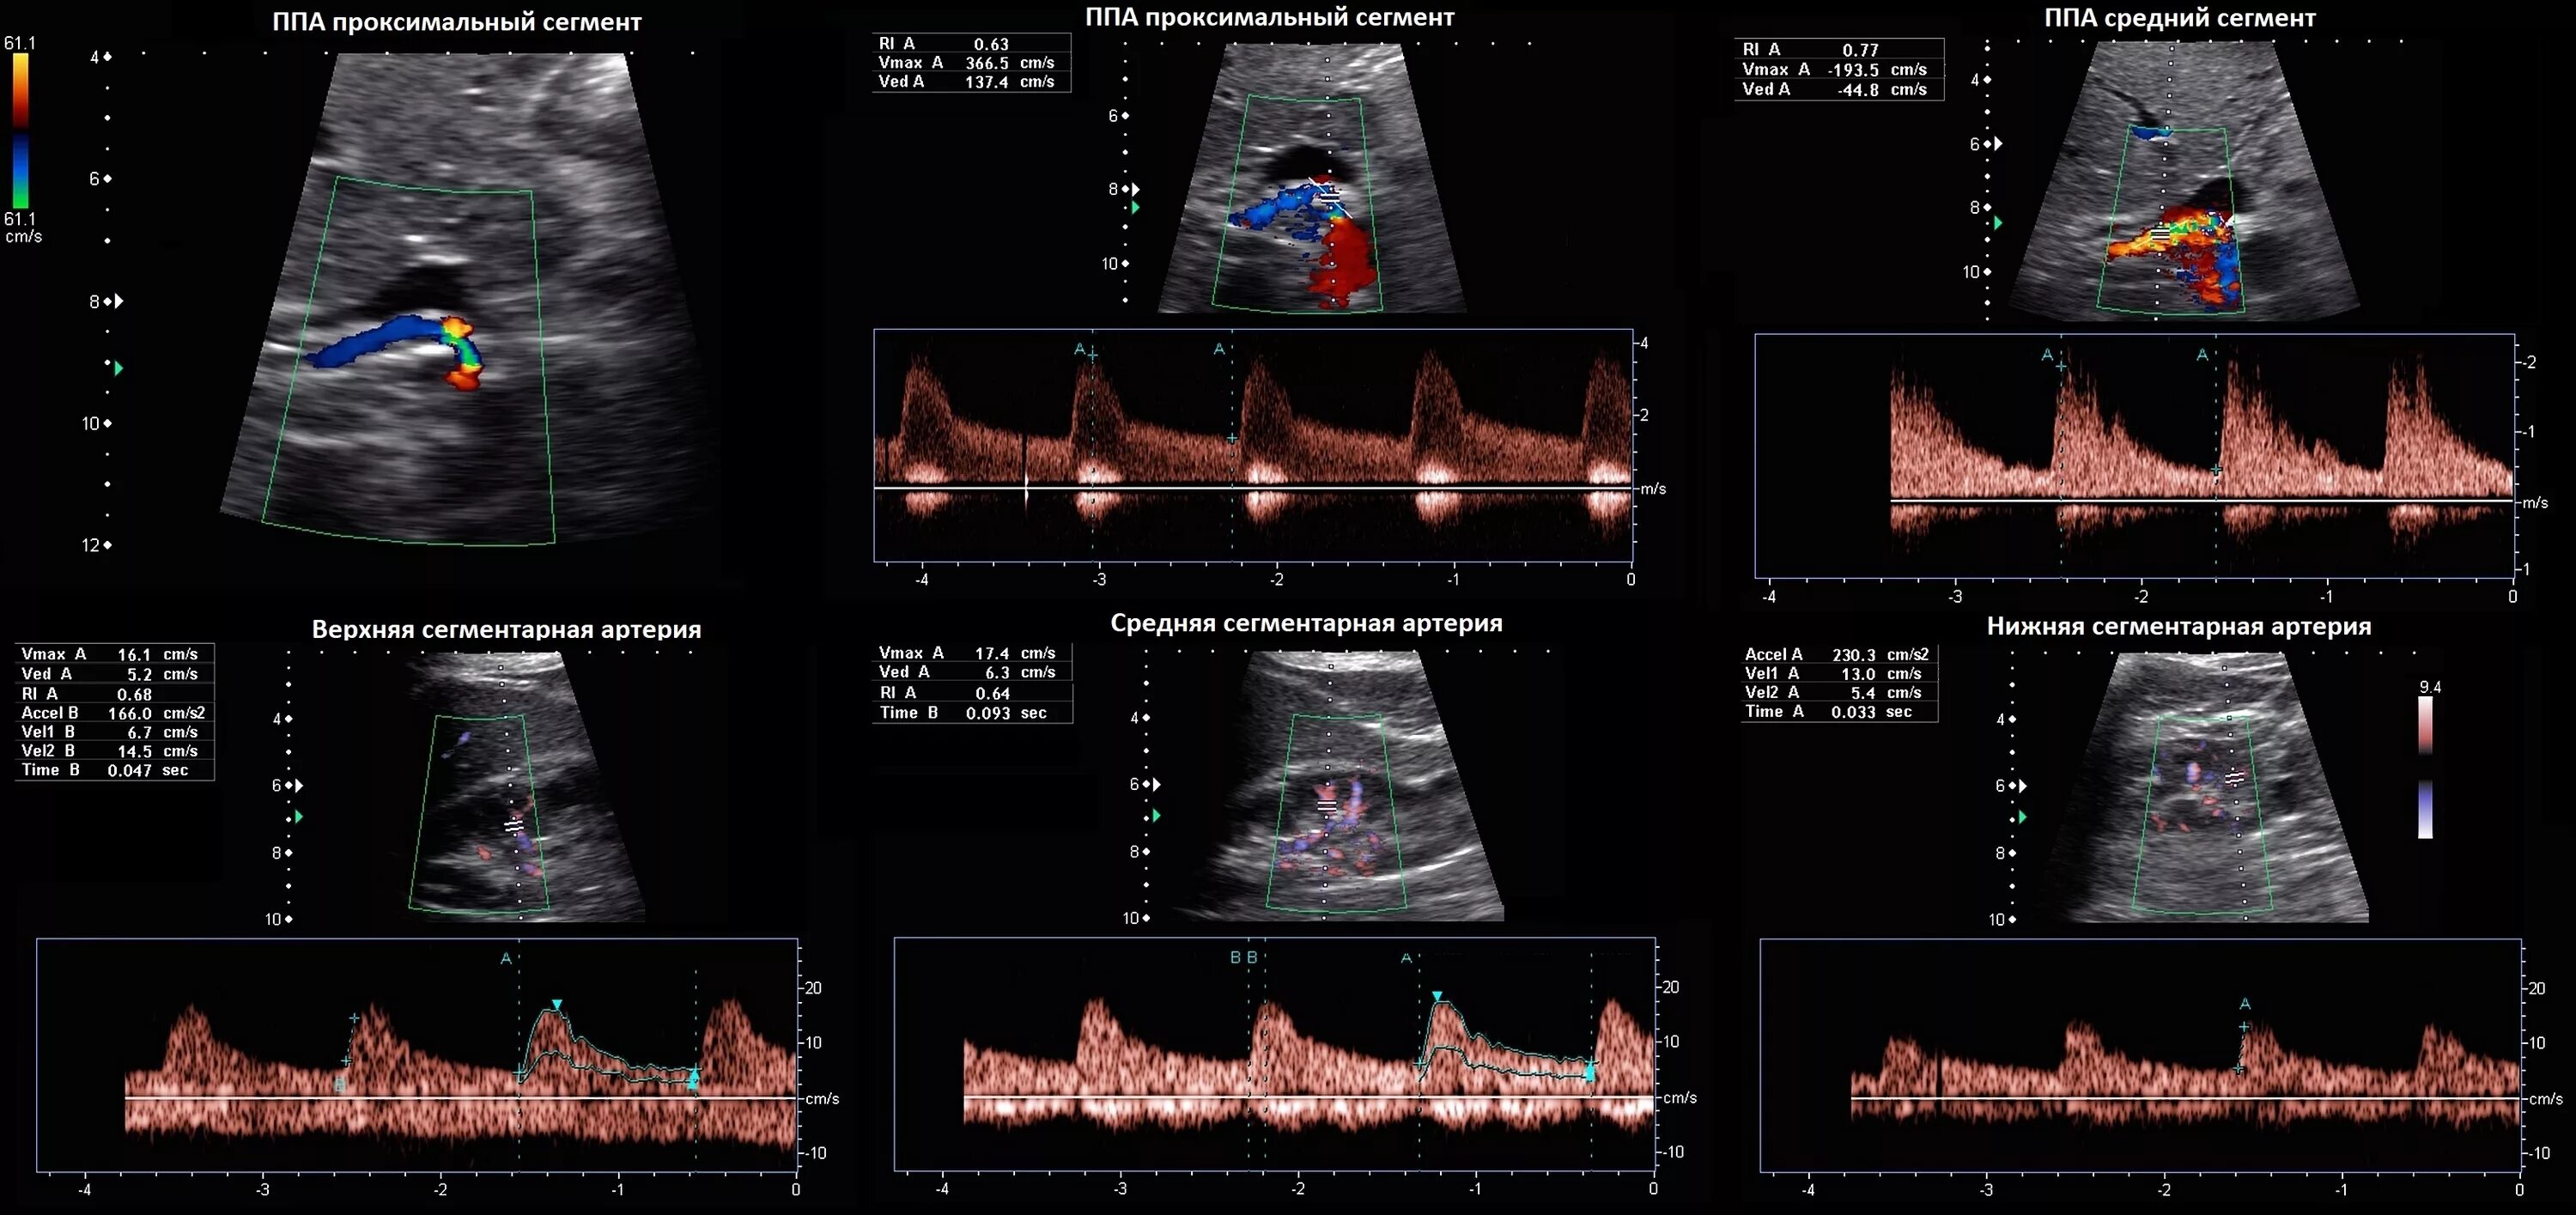

Нормы узи сосудов